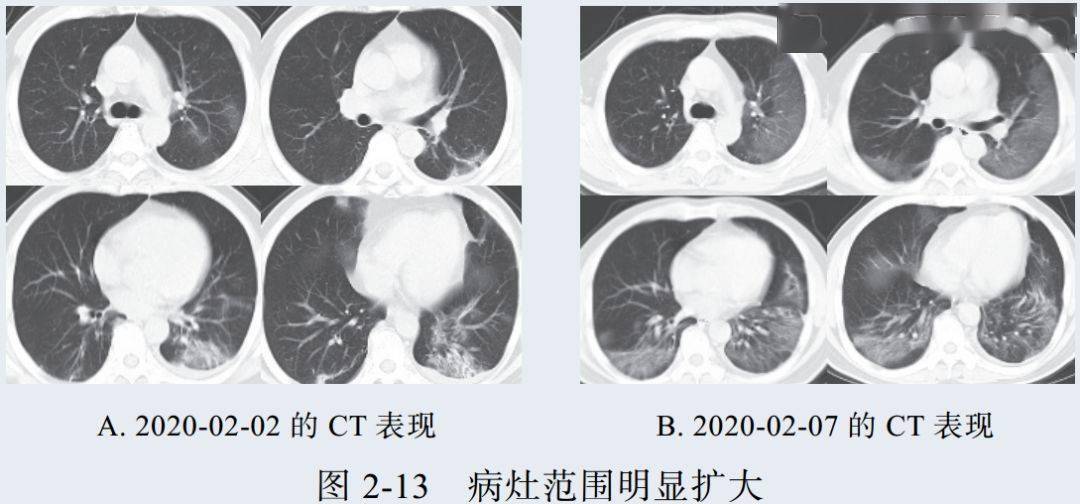

新冠肺炎大多数病例进展迅速,复查 CT 影像发生明显变化

表现为病灶数目明显增多,范围明显扩大,密度增高,病灶分布由外周向中央推进

根据既往 SARS 病理学机制,提示为肺泡腔内聚集大量细胞渗出液、间质内血管扩张渗出;肺泡连通起来形成融合态势(图 2-11)

图 2-11 病灶数目增多、范围扩大 (A-D)